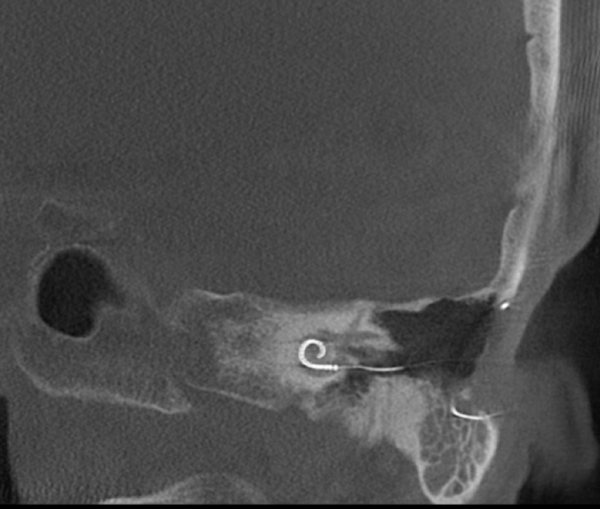

Both patients were imaged immediately with CBCT using SCANORA® 3Dx (Soredex, Tuusula, Finland). The field of view (FOV) was 140 x 165 mm and voxel size 0.2 mm. Imaging parameters were 90 kV, 8 mA, 4.00s. Standard 1 mm axial, coronal and sagittal reformations were made, as well as MIP and 3D reconstructions using OnDemand3D™ software (Cybermed, Seoul, South Korea).

CBCT proved to be optimal for imaging of these implants because of the superior bony delineation and nearly artefact free images. All four parts, i.e. the receiver stimulation part, extracochlear electrode implanted on the surface of the temporal bone, the extracochlear electrode plate and the intracochlear electrode array could be well imaged with CBCT.

On CBCT all four of the important parts of the implant were very well seen both on the axial slices and three dimensional surface reconstruction images. The implant is placed on magnetic plates, and the extracochlear part was seen in an abnormal separated position. The intracochlear electrode array showed no signs of separation in either of the cases. The intracochlear electrodes were well seen in both of the cases.

The optimal images of these two patients are shown in the radiographic illustrations in Figures 1-7.

Figure 1: Patient 1 - Sagittal oblique reformatted CBCT image showing the intracochlear portion of the implant.

Figure 6: Sagittal thick MIP image of the implant of patient 2.

Figure 7: Patient 2 - Sagittal oblique image of the intracochlear portion of the implant.